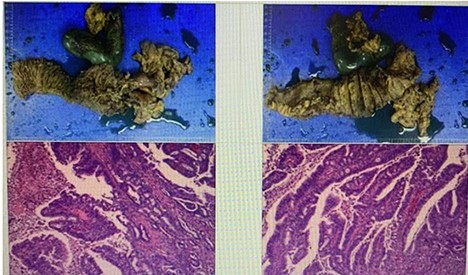

Left-image is postoperative fluoroscopy confirming smooth passage of contrast in the remnant stomach and the gastrojejunostomy with no stenosis or flaccidity; Right-image confirming smooth passage of contrast in the choledochojejunostomy and pancreaticojejunostomy.

Postoperative pathological report (Fig 5) indicated the following:

Tumor site: pancreatic-head.

Pathological stage: T3N0M0.

Tumor size: 7.3 × 6.8 × 3 cm.

Histological type: ductal adenocarcinoma.

Histological grade: grade IIA.

Surgical margin invasion: there is a cancer involvement found into the duodenal wall, no cancer involvement found in the gastric cutting edge, common bile duct stump.

Lymph node involvement: no lymph node involvement.

Nerve invasion is present. However, no vascular invasion was seen.